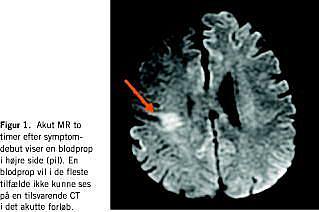

Der er flere mulige differentialdiagnoser til akut apopleksi (transitorisk cerebral iskæmi (TCI), migræne med aura, Todds parese eller pseudoapopleksi), som kun forløbet eller supplerende undersøgelser kan afsløre. Det største kliniske problem er dog, at debuttidspunktet for apopleksien ikke altid er let at fastlægge. Dette skyldes afasi, neglect eller bevidsthedsforstyrrelser hos den uobserverede patient, der lider af svær apopleksi og bliver fundet af arbejdskammerater eller pårørende, eller når apopleksien opstår under søvn. Nye magnetisk resonans (MR)-teknikker med diffusions- og perfusions-MR-skanning kan løse disse problemer, hvorved håbet er, at både effekten og sikkerheden under trombolysebehandling kan forbedres. Ved at benytte MR-teknikken (Figur 1) kan patienter udvælges på et patofysiologisk grundlag.

Ved obstruktion af et cerebralt kar går neuronerne centralt i området hurtigt til grunde, og der opstår et iskæmisk infarkt. Rundt om infarktet er der imidlertid hos de fleste patienter væv, som kun kan klare sig i en vis tid (fra timer til op til et døgn) via kollateral blodforsyning: den iskæmiske penumbra. Som tiden går, vokser infarktet ind i den iskæmiske penumbra. Symptomerne i den akutte fase stammer både fra selve infarktområdet og den iskæmiske penumbra, uden at det klinisk kan afgøres, om der stadig er væv, der kan reddes. Ved trombolysebehandling øges chancen for en hurtig opløsning af blodproppen og dermed en hurtigere reperfusion af det iskæmiske væv, hvorved der kan iagttages betydelig bedring af de neurologiske symptomer. Ved diffusions- og perfusions-MR-undersøgelse forud for trombolysebehandling kan det afgøres, hvor stort infarktet allerede er, og om der er en iskæmisk penumbra og dermed mulighed for at redde iskæmisk væv fra at gå til grunde.